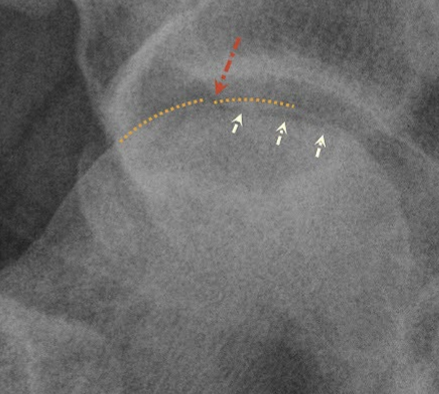

Crescent sign = radiolucent subcortical band representing a fracture line

Later Stages = flat femoral head, combo of sclerotic (dense) and lytic (translucent) regions